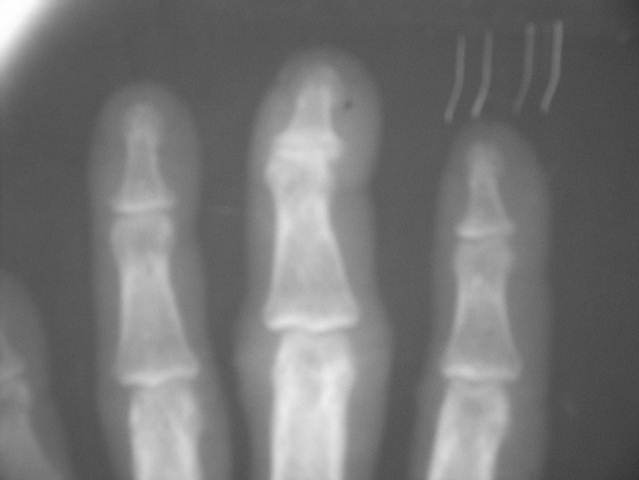

PSORIATIC ARTHRITS